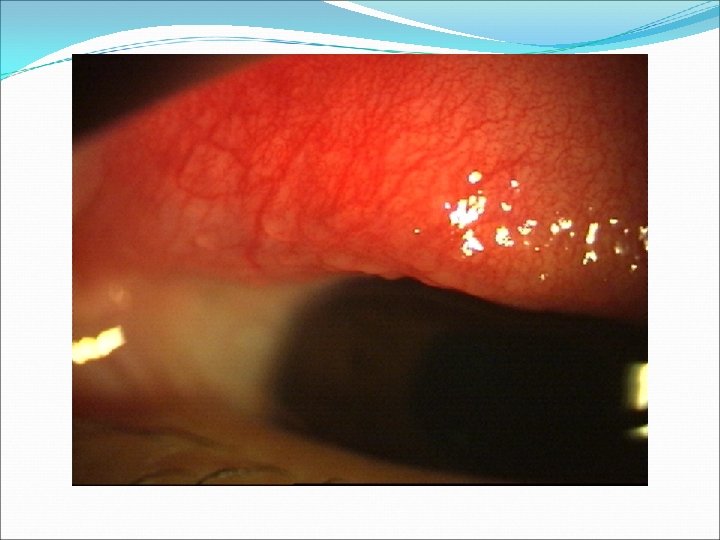

FOLİKÜLER REAKSİYON Viral konj. Klamidyal konj. Perinaud Oküloglanduler Sendromu Medika mentoza

Tek taraflı sulanma, kızarıklık, batma ve fotofobi İkinci göz 1 -2 gün sonra, daha hafif Kapak ödemi ve LAP Folliküler konjonktivit Şiddetli enfeksiyonlarda konjonktival kanama ve pseudomembran oluşumu